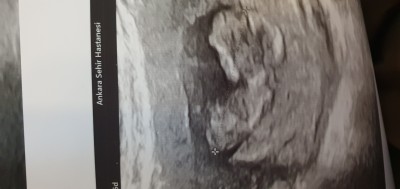

2 oglandan sonra 3. Gebeyim kız istiyorum anlayan yazabilir mi

image

Bacım üzülme ama buda erkek gibii

Ve bildiniz oğlan